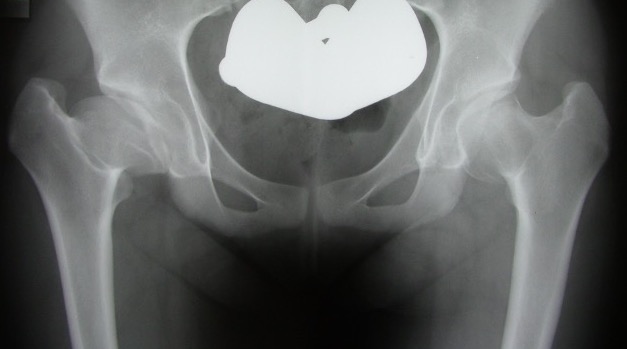

4. Remodelling

Duration : Occurs until skeletal maturity

Xray - May have flattening of the head and neck